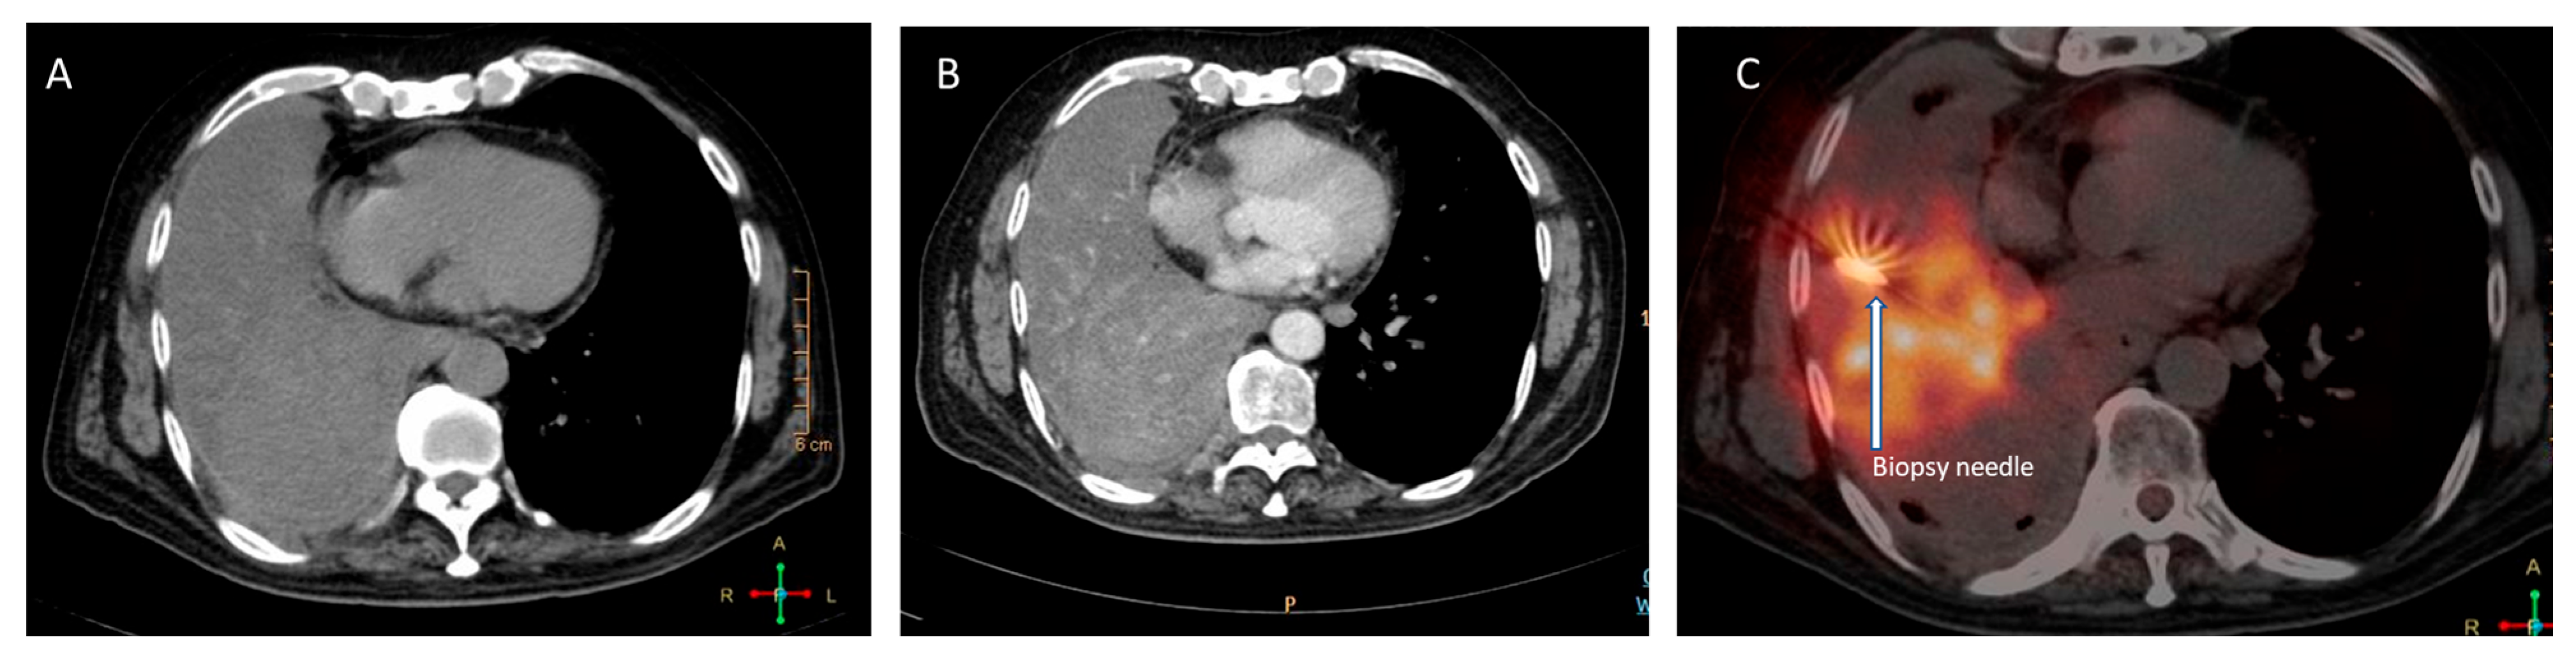

18]. PET/CT permits the identification of FDG-rich portions of large necrotic lesions and aids in distinguishing consolidation from live-tumour tissue (

Figure 3). FDG PET/CT guides the biopsy to the most metabolically active section of the lesion, minimising sample errors that could come from biopsying areas with necrosis or fibrosis [

19]. In cases of patient with multiple lesions, PET-CT scans also enable the determination of the best accessible spot for biopsy. Biopsy of the most accessible lesion can minimise sampling errors and reduce the incidence of complications associated with the procedure [